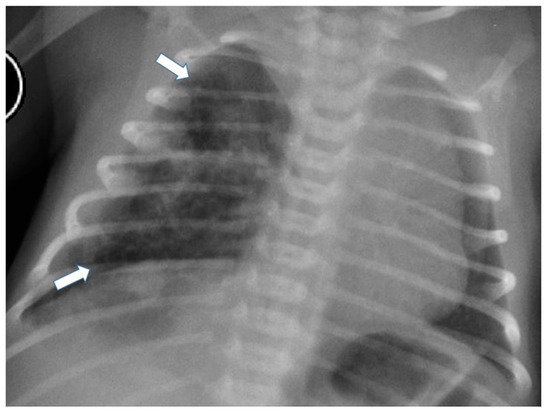

3.4.3. Congenital Lobar Hyperinflation